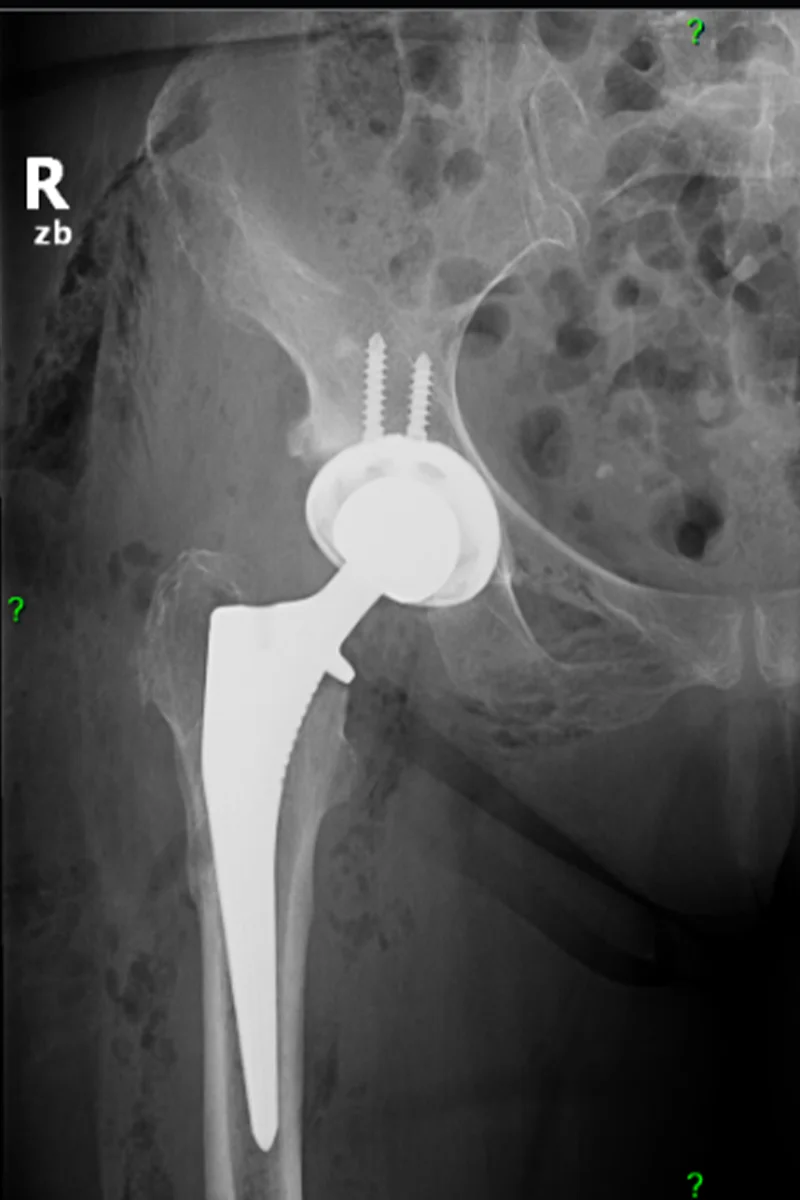

A combnyaktörés revíziós műtétének menete és lehetőségei

A revíziós műtét akkor válik szükségessé, ha a korábbi beavatkozás után nem javul a beteg állapota, vagy szövődmények jelentkeznek.

Ezek az eljárások általában hosszabb ideig tartanak, mint a hagyományos protézis műtétek, mert gyakran csontpótlást kell végezni, illetve heges szövetekkel dolgozni. A beavatkozás nagyobb tapasztalatot igényel, de a korszerű technológiák – mint az egyedi implantátumok, precíz képalkotás és robotnavigációs technológiák – jelentősen növelik a siker esélyét.